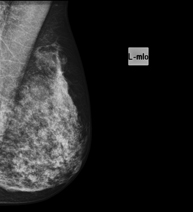

Mamografia

Els estudis de Mamografia obtenen imatges generades a partir de raigs X de dosi molt baixa que permeten detectar les diverses patologies dels teixits mamaris (en especial el càncer de mama), tant per al cribratge (screening) ginecològic com per al diagnòstic dirigit. La mamografia pot ser intervencionista amb punció de quists, biòpsia estereotàxica, marcatge prequirúrgic i galactografia.